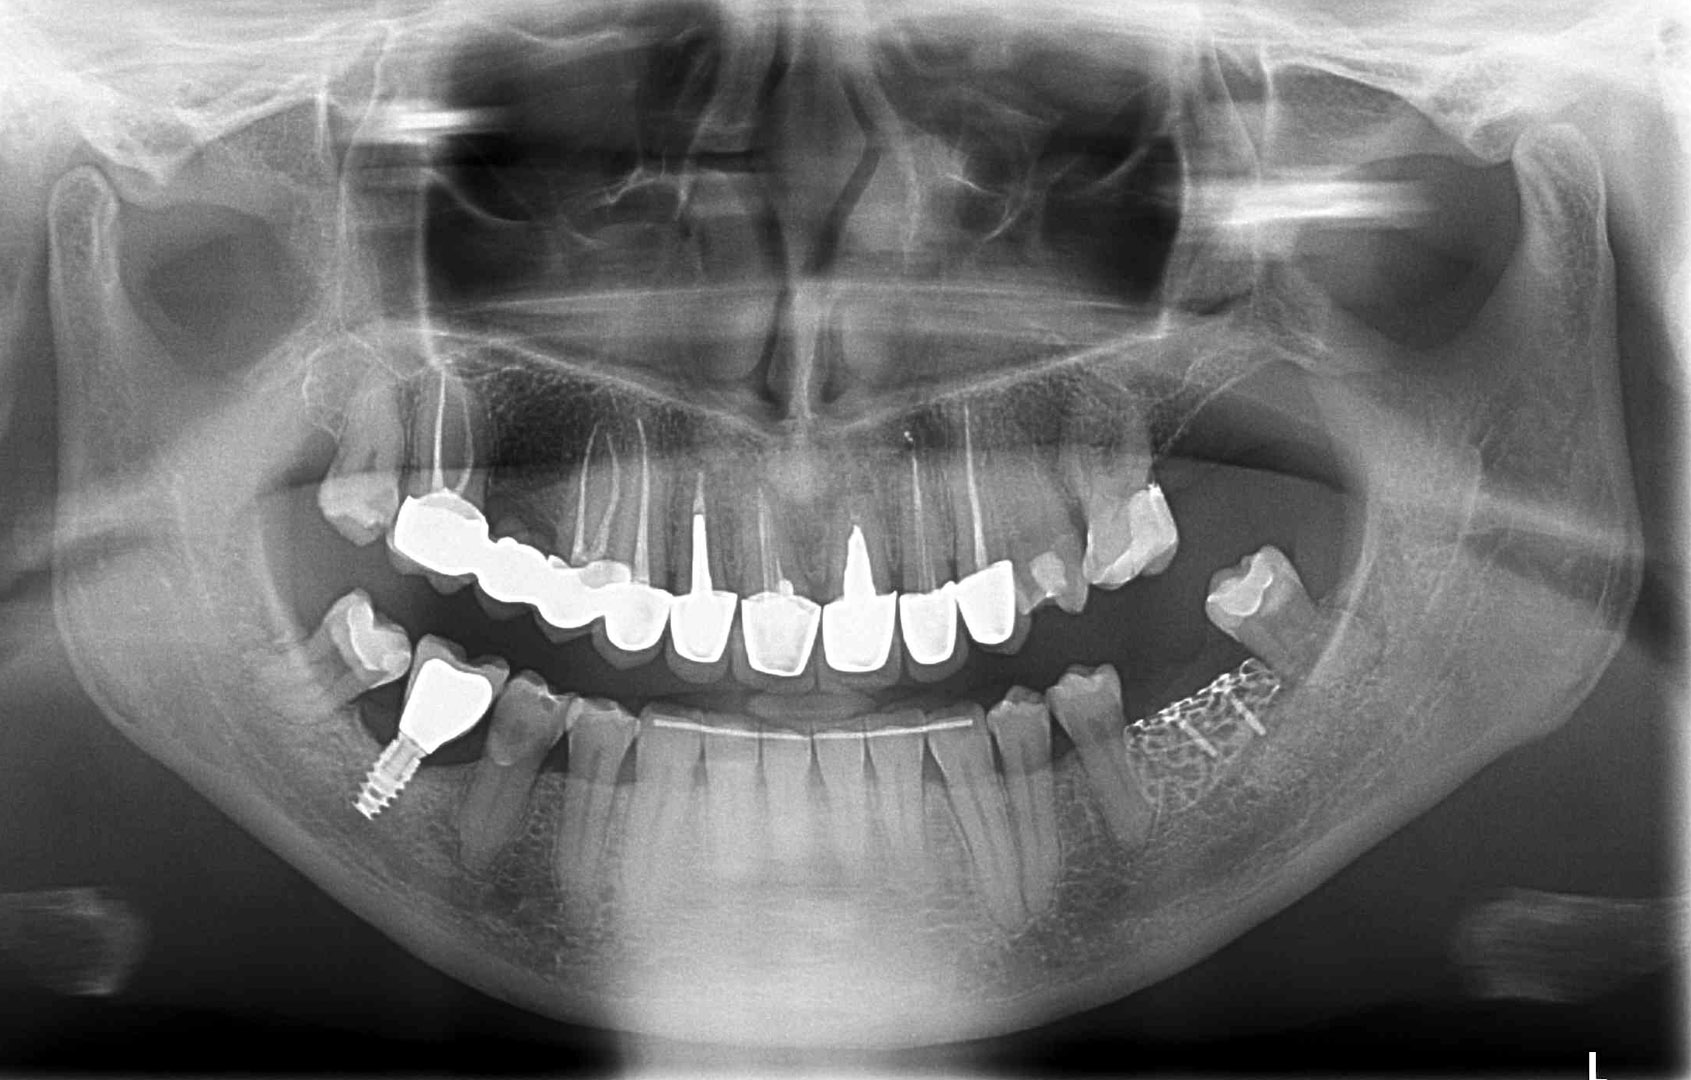

Przed podjęciem leczenia należy określić stopień zaniku kości szczęk oraz żuchwy. W tym celu przeprowadza się badanie kliniczne oraz odpowiednią diagnostykę obrazową pacjenta. Uwzględnia ona zdjęcie panoramiczne OPG jako podstawę dwuwymiarowego obrazowania podłoża kostnego oraz możliwe jest badanie tomograficzne CT lub bardziej precyzyjna tomografia stożkowa CBCT. Opcjonalnie wykorzystywana diagnostycznie tomografia pozwala na bardziej wnikliwą ocenę stopnia zaniku kości w trójwymiarowym, przestrzennym obrazie.